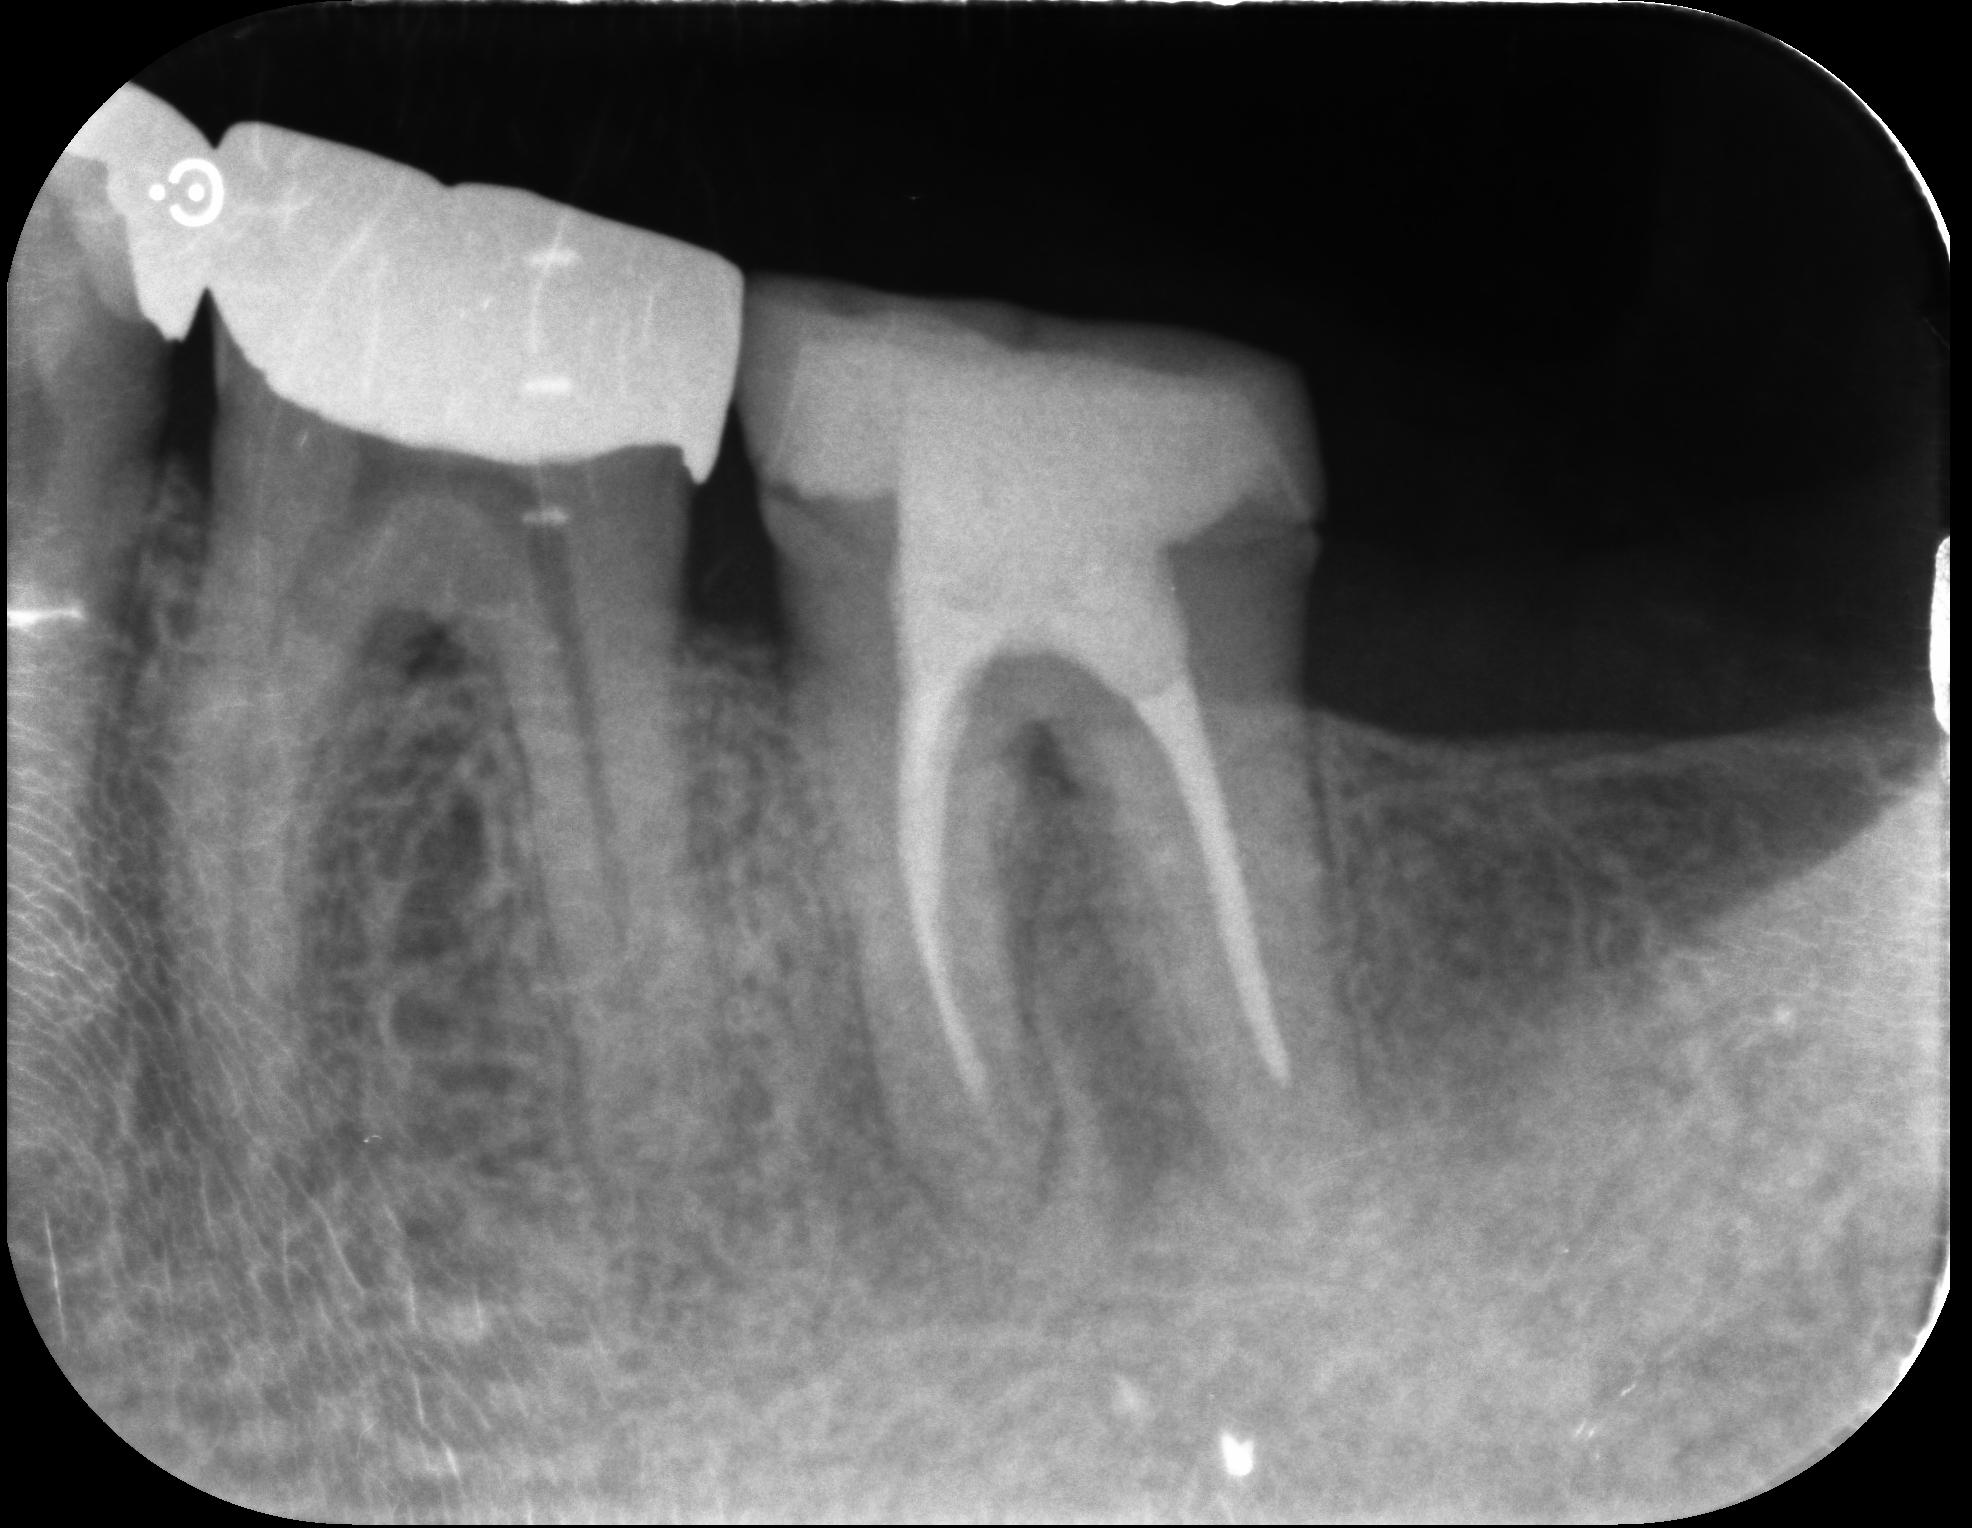

患者様の移植に使用する歯が智歯(ちし=親知らず)であれば保険適応となっており、移植後に根管治療は必要なものの、生着するとご自身の歯をそのままお使い頂けるため、とてもメリットのある治療です。

そこで、後ろにある親知らずを抜歯して、歯牙移植(自家歯牙移植=ご自身の歯を使用して移植)を行うこととなりました。

経過